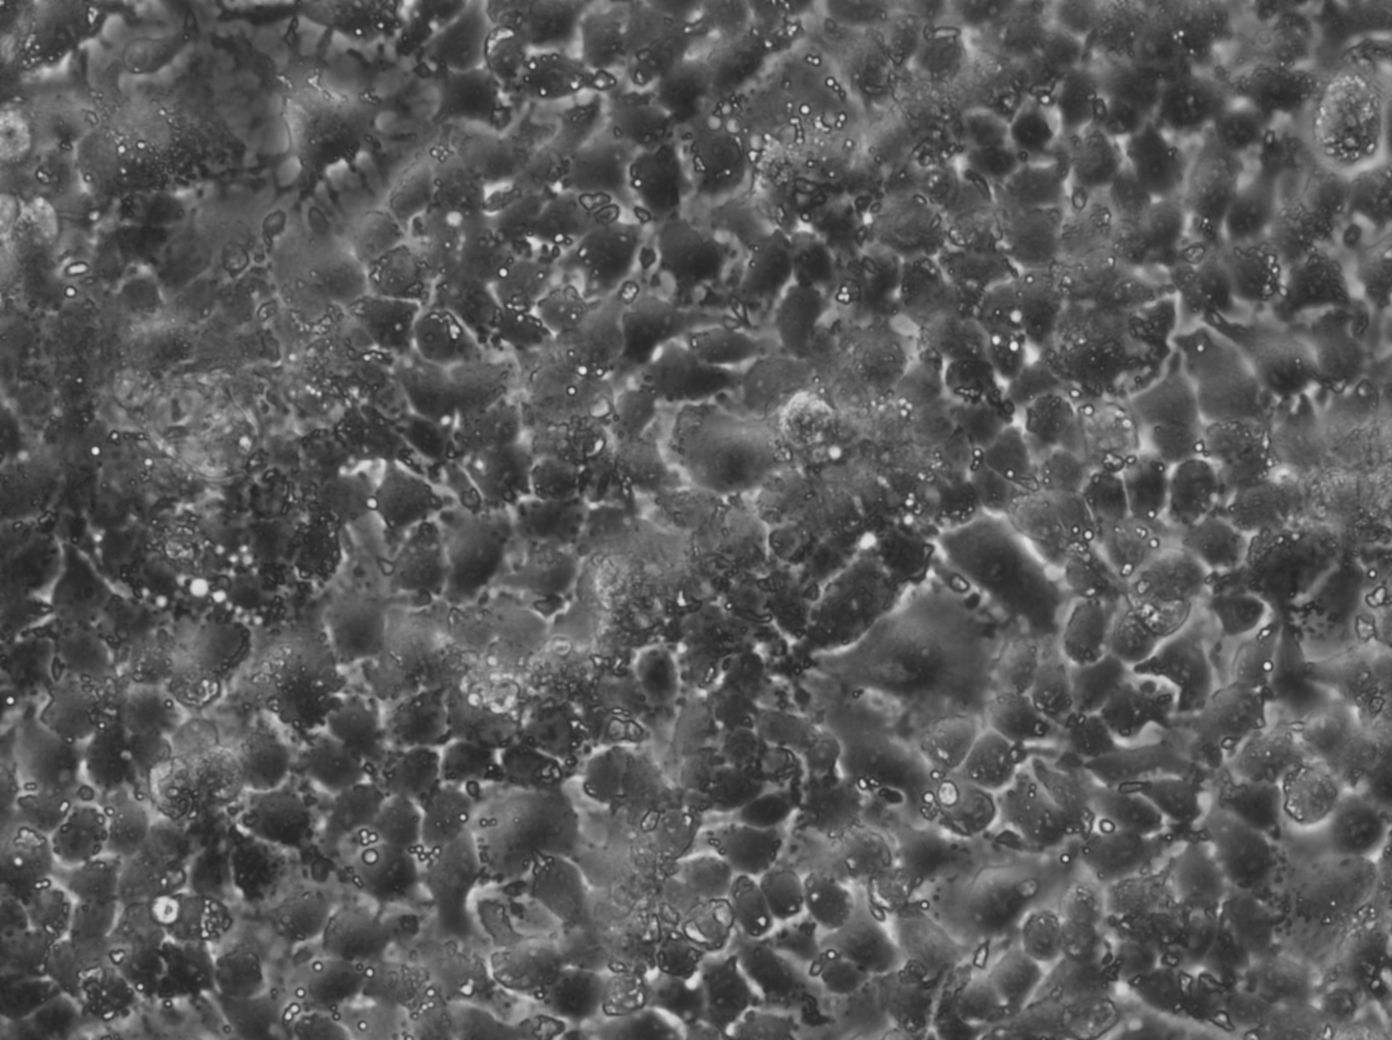

Morphology: Epithelial-like

Growth Properties: Adherent

Description: HuH7 was established in 1982 by Nakabayashi et al. from a 57-year-old Japanese male with well differentiated hepatocellular carcinoma.